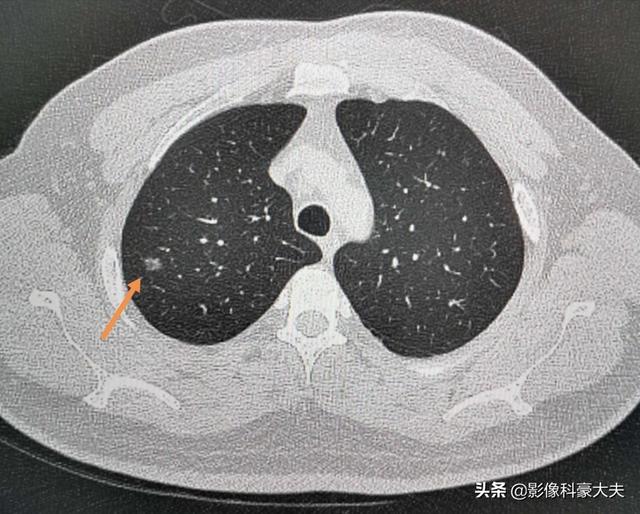

9ミリのin situ腺がんは、自覚症状もなく、身体機能もすべて正常だが、CTでしか早期発見できず、手術で切除した。

このような器具を使わず、聴診器だけでは、3~5年後に進行した段階で発見されるのが怖い。

こうした先進的な装置により、肺がんの5年生存率は過去20年間で8%から20%近くまで上昇した。今後数年間で、より多くの人々が早期がん検診に注意を払えば、この数字は劇的に上昇することは間違いない!かつての胃がんの予防と制御のように。